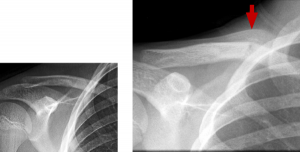

BELOW: Day 1 – normal RIGHT: Week 3 – fracture and callus